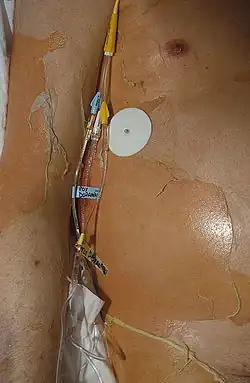

| Characteristic skin loss of toxic epidermal necrolysis | |

Nearly all people with TEN have oral, eye and genital involvement as well. Painful crusts and erosions may develop on any mucosal surface.[9] The mouth becomes blistered and eroded, making eating difficult and sometimes necessitating feeding through a nasogastric tube through the nose or a gastric tube directly into the stomach. The eyes can become swollen, crusted, and ulcerated, leading to potential blindness. The most common problem with the eyes is severe conjunctivitis.[10]